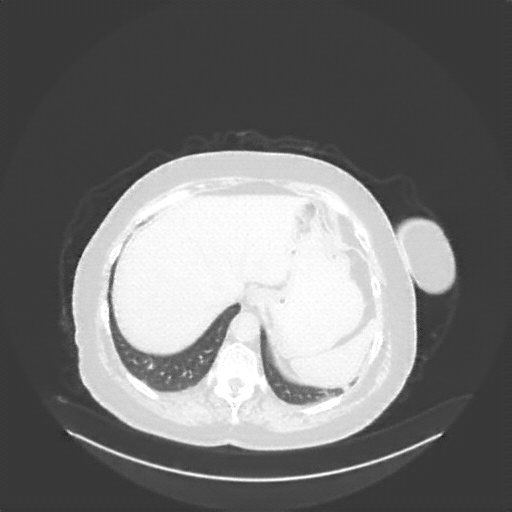

Image Grid

4Γ—3 grid: Rows show different image types (Original NATIVE, Reconstructed NATIVE, Original VENOUS, Generated VENOUS), Columns show windowing techniques (No Window, Lung Window, Mediastinum Window)

Original NATIVE CT scan (input)

No window - Raw intensity values

Reconstructed NATIVE CT scan (cycle consistency)

Original VENOUS CT scan

Generated VENOUS CT scan (A→B translation)